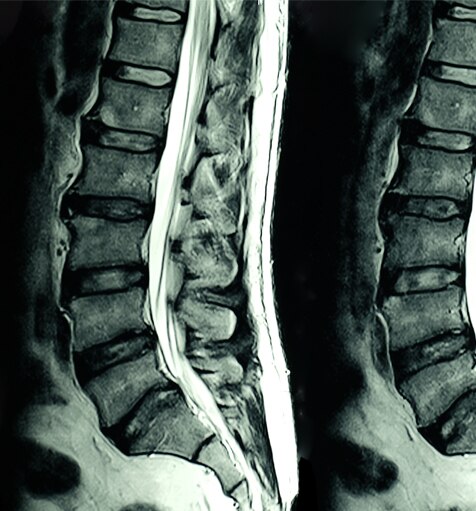

L’IRM (imagerie par résonance magnétique) est une technologie d’imagerie non invasive qui produit des images en coupe du corps. Elle est utilisée dans de nombreuses applications médicales, notamment : imagerie musculo-squelettique, gastro-intestinale, oncologique, cardiovasculaire et neurologique. L’IRM peut différencier les structures des tissus mous sur tous les plans, ce qui en fait un outil de diagnostic précieux.

Les scanners IRM génèrent un champ magnétique fort qui, combiné à des courants de radiofréquence, stimule des molécules spécifiques dans le corps.

Le comportement de ces molécules permet de générer une image en trois dimensions des tissus corporels. Voici quelques exemples d’images obtenus par IRM :